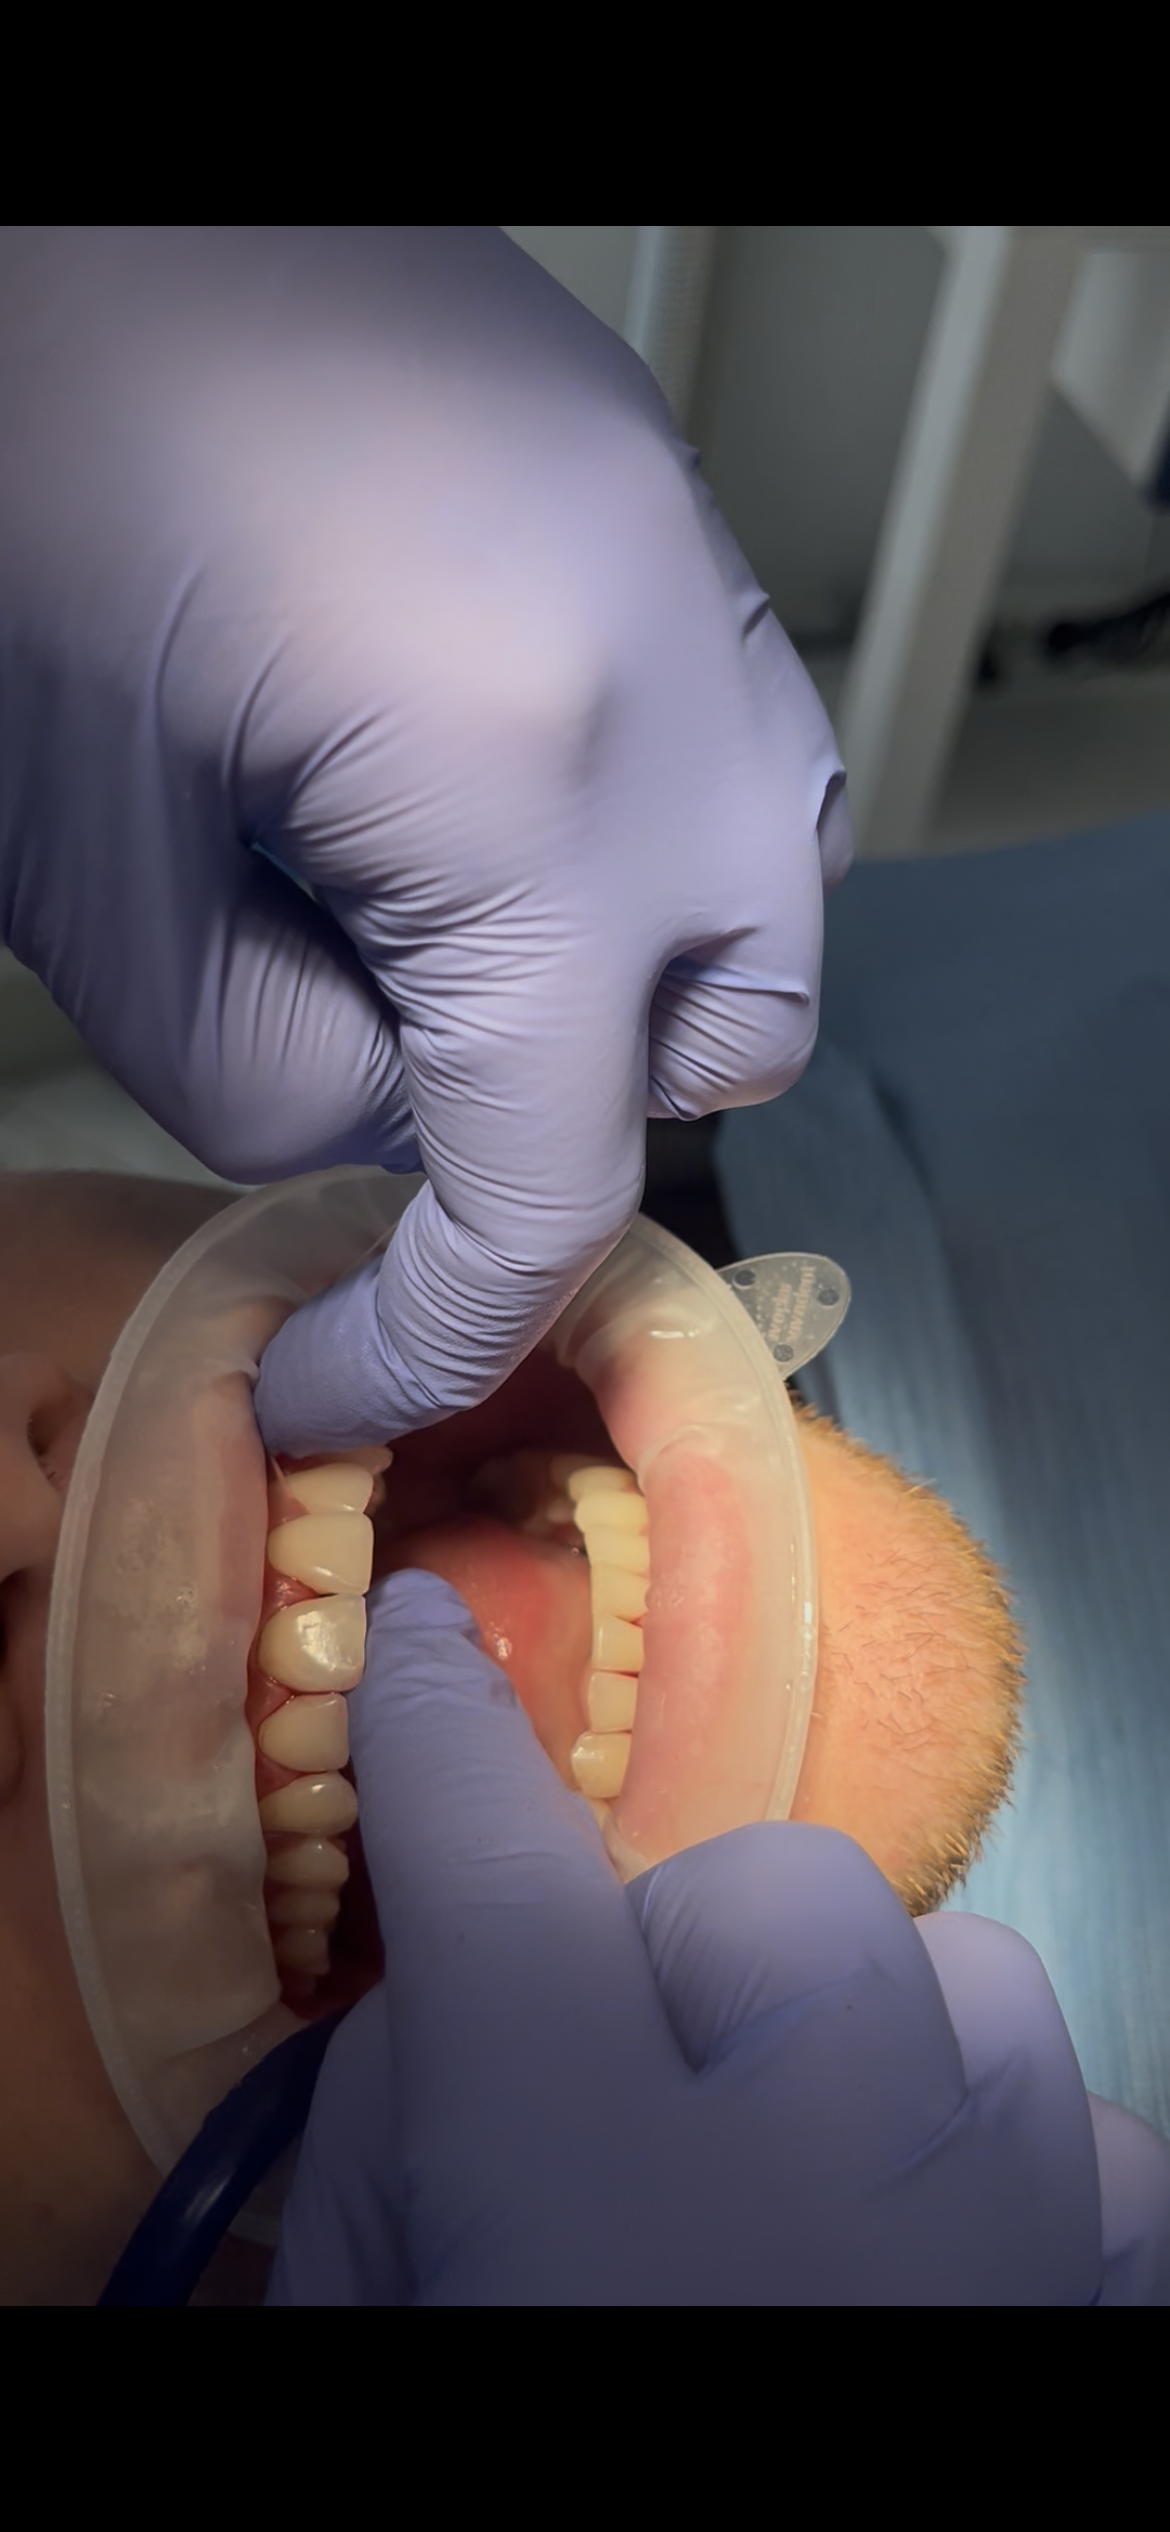

Quando si parla di igiene orale quotidiana, la maggior parte delle persone pensa subito allo spazzolino e al dentifricio. In realtà, per mantenere davvero sani denti e gengive, esiste un alleato fondamentale che spesso viene sottovalutato: il filo interdentale. Perché lo spazzolino da solo non basta Lo spazzolino è essenziale per rimuovere la placca batterica dalle…